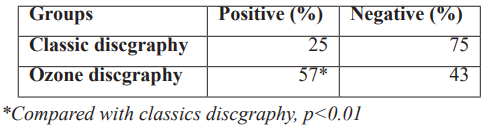

Table 3: Compare in the percentage of evoked pain by classic and ozone discography.